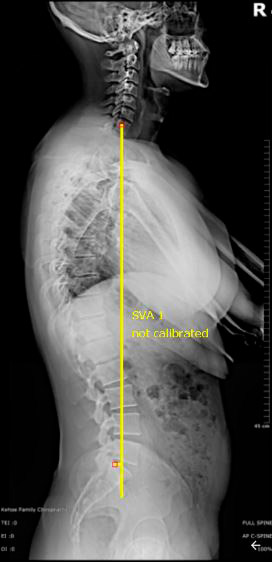

No plano sagital, observe que o alinhamento ultrapassa os 5cm do sacro, inclusive ultrapassa as cabeças femorais, demonstrando grave desequilibro sagital. Este tipo de desequilíbrio acarreta baixa qualidade de vida. (Fig. 3)

Por outro lado, no plano coronal, a paciente apresenta um desvio do eixo maior que 3cm, demonstrando desequilíbrio nos dois planos. Este é o pior cenário para o paciente que sofrerá de dores crônicas intratáveis se não corrigido cirurgicamente.

Fig. 4 – Desalinhamento coronal >3cm >5cm.